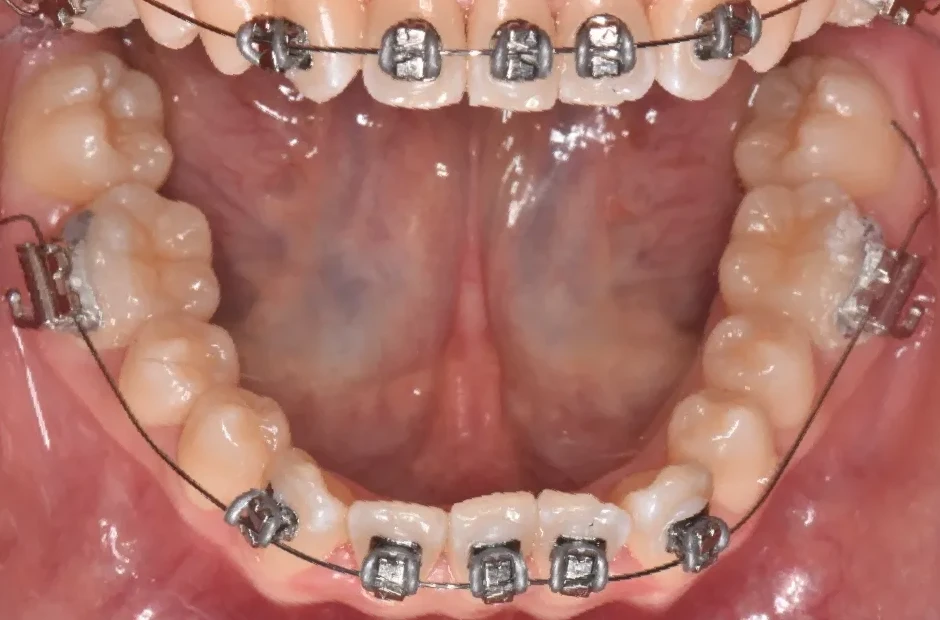

反対咬合

| 診断名・主訴 | 前歯反対咬合 |

|---|---|

| 年齢・性別 | 12歳・男性 |

| 治療期間・回数 | 1年半 18回 |

| 治療に用いた主な装置 | リンガルアーチ(前方誘導弾線) |

| 抜歯部位 | なし |

| 治療費 | 35万円(税抜) |

| リスク・副作用 | 装置による違和感・疼痛・歯肉退縮・歯根吸収・虫歯のリスクなど |

治療前

治療中

治療後